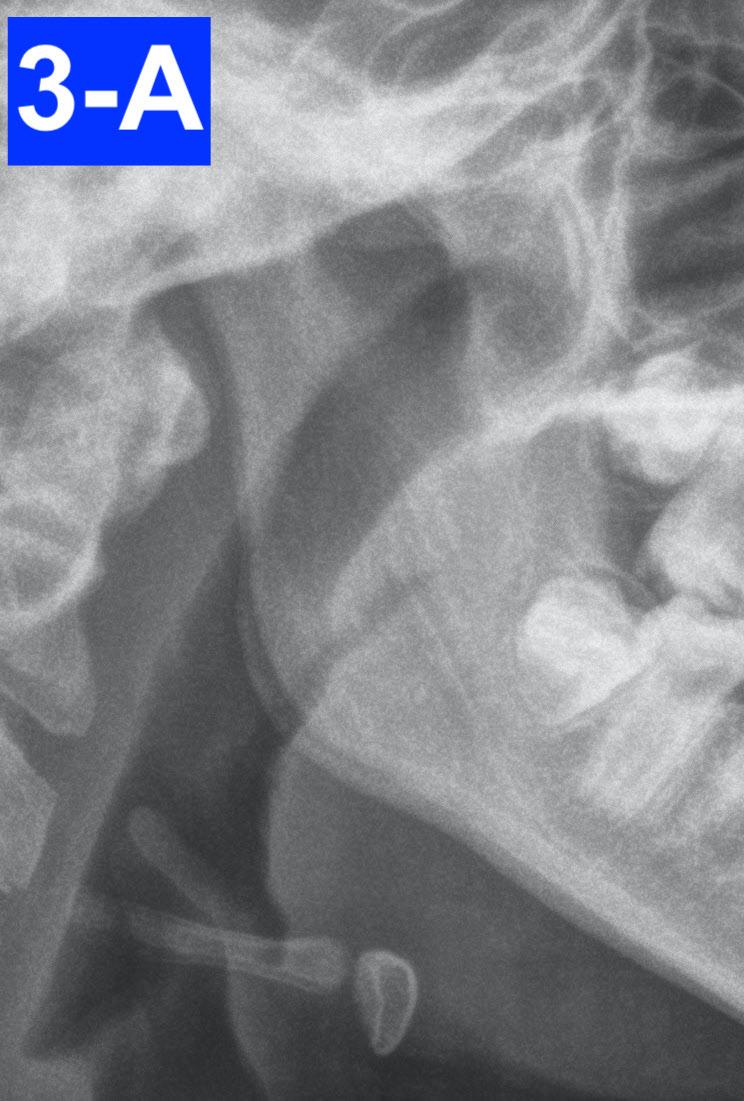

Clinical appraisal of the airway revealed a patent airway: Pharynx - 10/10 mm, Oropharynx - Mallampati IV, Nasopharynxvery patent (Figures 3-A, B, C, D, E).

Fig. 3-A: Pharynx